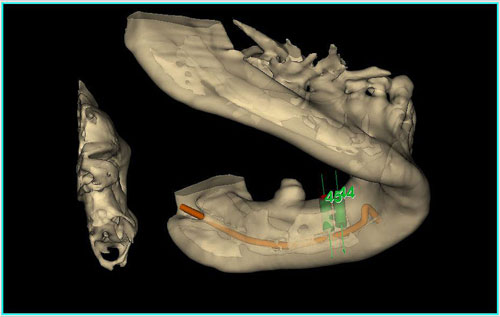

Mientras dichos movimientos ortopédicos se producen (período que supondrá otros seis meses), estudiamos los actos quirúrgicos a realizar en los cuatro implantes que pondremos. De acuerdo al estudio Desatascan realizado observamos tres situaciones diferentes: 1º-El Primer Molar Inferior Izquierdo, lo instalamos mediante Cirugía Minimamente Invasiva , con la aplicación de una Férula Quirúrgica Obtenida de los datos del scanner tratados con un programa de CMI (Cirugía Minimamente Invasiva), previa prueba en un modelo estereolitográfico, ya que la altura ósea era apenas de 9 mm. 2º- El Primer Molar Superior Derecho, se implantará mediante una ligera Elevación Atraumática (Trans alveolar) de Seno una vez logrado el espacio mesio distal necesario. 3º- El Incisivo Central Superior Derecho ausente, cuenta con un sustrato óseo prácticamente inexistente. El espesor de la tabla era de menos de 2 mm. Los caminos posibles a seguir para contar con una Rehabilitación de piezas independientes son dos: Optamos por esta segunda opción por ser menos cruenta y no necesitar de una zona dadora. Técnica esta que pondremos en práctica en dos etapas diferidas: 1º-Incisión horizontal palatinizada, incisiones peri rodetes gingivales e incisiones de descarga. Dilatación que comenzamos con dos incisiones de descarga sobre la cortical vestibular realizadas con disco. y el comienzo de la dilatación propiamente dicha mediante una hoja de bisturí, para luego seguir con un periostótomo . Recién después de alcanzada una cierta separación de la cortical vestibular de la palatina, empezamos con los dilatadores roscados. En este punto podríamos haber utilizado sin riesgos un Implante de 3,8 mm de diámetro, pero a fin de mejorar la estética del pilar emergente decidimos rellenar con material osteoconductor y osteoinductor (BiOss) y cubrir mediante membrana reabsorvible ( Bio Guide). 2º-Implantación seis meses después. Mientras se van cumpliendo los tiempos antes mencionados, y comprobamos reiteradamente la funcionalidad de la oclusión con los provisorios, tomamos impresiones definitivas y construimos primero el maxilar inferior, para definir en primer término la porción inferior de la Guía Anterior., y a nivel posterior Curvas y Microplanos. Para luego realizar los cuadrantes premolar- molar del superior: La espera de la regeneración ósea y sus tiempos pertinentes, más la espera de los tiempos de la implantación, nos obligaron a modificar las etapas del protocolo D.AT.O de manera de mantener la –D- mediante el sector superior de la GA. en provisorios, mientras fuimos resolviendo en forma definitiva los demás sectores. Ya pasados los meses necesarios para recrear un hueso adecuado en el área del Incisivo Superior Derecho, procedemos a resolver la implantación de dicha zona, observando que todo el esfuerzo dedicado al mismo había sido inútil, ya que la formación de hueso se produjo minimamente. Cuatro meses después tomamos impresiones del sector Antero Superior de la Guía Anterior, incluyendo el arrastre de un transfer . Seguimos modelando la encía con un nuevo juego de provisorios. Y se construye entonces el sector superior de la Guía Anterior. Se efectúa un control radiográfico a los 6 meses. Se ha intentado mostrar en esta Rehabilitación, que a pesar de las distintas circunstancias de cada paciente, siempre debemos tener en cuenta la necesidad de ejercer la DESOCLUSIÓN del caso como prioridad número uno, para luego perseguir la ALINEACIÓN TRIDIMENSIONAL de las arcadas y obtener así una OCLUSIÓN equilibrada. D.AT.O. ES EL PROTOCOLO QUE DEBEMOS SEGUIR EN TODA REHABILITACIÓN. BIBLIOGRAFÍA 1)William Mc Horris,B.S.,D.D.S. Oclusión. Con especial énfasis sobre :El rol funcional y parafuncional de los dientes anteriores. 2)Von Spee , Craff(Anatomista alemán, describió la curva de compensación de la articulación de molares y premolares).CURVA DE SPEE 1.89 3)Stuart,D.”Some aspects of the inervation teeth.”Procedings of Royal Society of Medicine.20:1675,19274)Muhleman,H. y Savdir,S”Tooth movility-its causes and significance”Journal of Periodontology ,36:153,Marzo ,Abril,1965. 4)Muhleman,H. Y Savdir,S”Toothmovility its causes and significance” Journal of Periodontology,36:153,marzo,abril,1965. 5-Oclusión y Diagnóstico en Rehabilitación Oral. 6-Anatomia Odontológica. 7-A contribution to the study of the movementes of the mandible. 8-Celenza F.W, Nadeskin J.F.,Oclusión.Situación actual. 9-D´Amico 10-Dawson P.E. 11-Huffman –Regenos. 12-Hobo S.-Takayama H.A. 13-Lucia V.O 14-Mc Horris. 15-Mc Horris. 16-Stuart C. 17-Vartan Veshnilian 18-Alvarez Cantoni H. AUTOR:Ratificación del Protocolo en Rehabilitación Bucal a pesar de las incidencias propias de cada caso clínico. A propósito de un caso.

Tridimencionalización mediante implatemetric y ensayo de colocación de implantes

Tridimencionalización mediante implatemetric y ensayo de colocación de implantes

Perforación de prueba en mod. esteorlit.